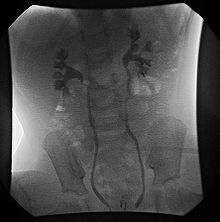

VCUG demonstrating bilateral Grade II (non-dilating) vesicoureteral reflux.

VCUG is the method of choice for grading and initial workup, while RNC is preferred for subsequent evaluations as there is less exposure to radiation. A high index of suspicion should be attached to any case where a child presents with a urinary tract infection, and anatomical causes should be excluded. A VCUG and abdominal ultrasound should be performed in these cases

Vesicoureteral reflux (VUR) is graded according to severity.[1]

• Grade I – reflux into non-dilated ureter

• Grade II – reflux into the renal pelvis and calyces without dilatation

• Grade III – mild/moderate dilatation of the ureter, renal pelvis and calyces with minimal blunting of the fornices

• Grade IV – dilation of the renal pelvis and calyces with moderate ureteral tortuosity

• Grade V – gross dilatation of the ureter, pelvis and calyces; ureteral tortuosity; loss of papillary impressions